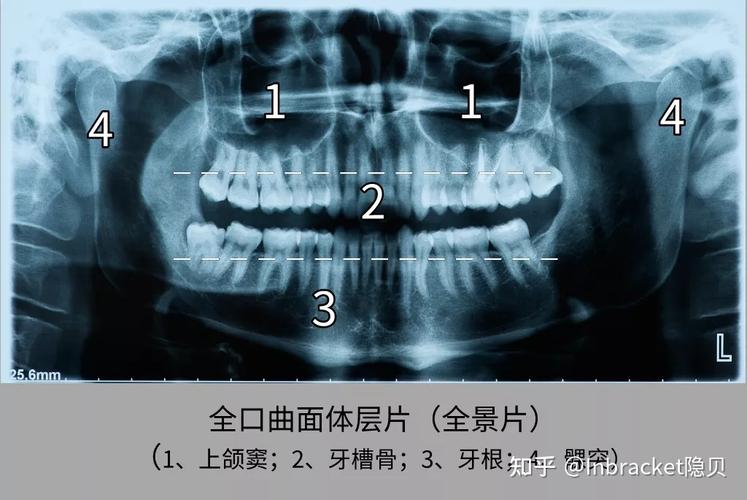

有一种x光片叫正畸前拍的牙片

全景牙片图片

全景牙片

牙片怎么看图解

牙片怎么看